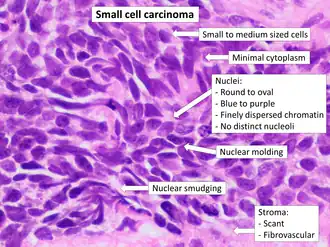

| Micrograph of a small-cell carcinoma of the lung showing cells with nuclear moulding, minimal amount of cytoplasm and stippled chromatin. FNA specimen. Field stain. | |

Small-cell carcinoma is an undifferentiated neoplasm composed of primitive-appearing cells. As the name implies, the cells in small-cell carcinomas are smaller than normal cells and barely have room for any cytoplasm. Some researchers identify this as a failure in the mechanism that controls the size of the cells.[32]